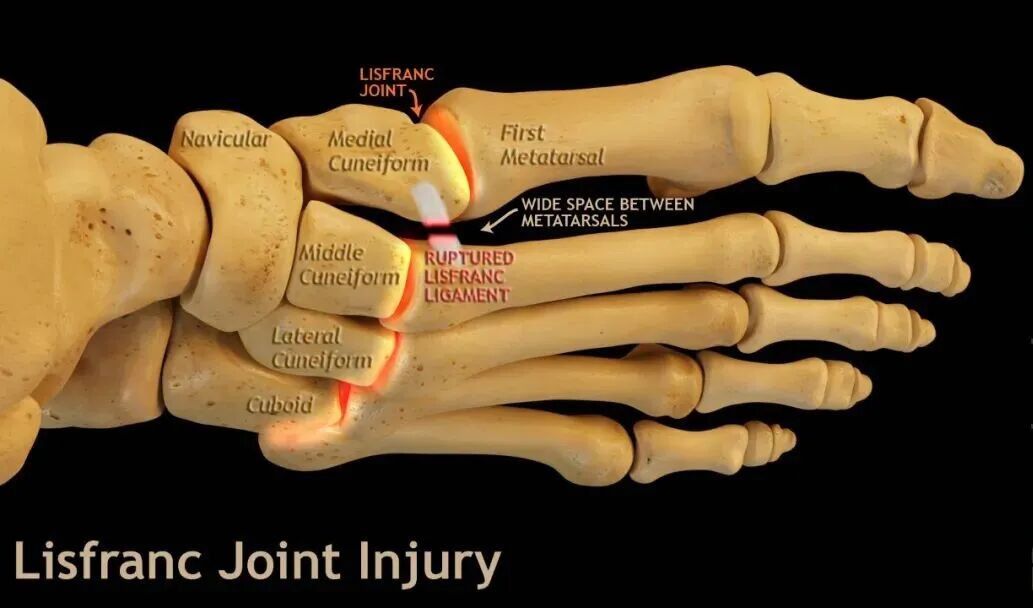

Lisfranc损伤是一种极为罕见的创伤,仅占所有骨科损伤的约0.20%。尽管许多医院仍采用切开复位螺钉内固定治疗单纯性Lisfranc韧带损伤,但尸体研究证实,纽扣钢板固定也能为单纯性Lisfranc韧带损伤提供足够的固定强度。本推文介绍采用标准TightRope:tm:固定单纯性Lisfranc韧带的技术方法,与同道分享学习。

单纯性Lisfranc韧带损伤的最佳固定方式仍存在争议。传统的主流固定方式为刚性固定,但所有刚性固定都会限制损伤足部内侧柱的活动,导致患者在剧烈活动时出现疼痛或螺钉断裂等问题。多项对比研究表明,弹性固定在韧带损伤治疗中可取得满意的疗效。采用标准TightRope:tm:治疗单纯性Lisfranc韧带损伤可提供可靠的固定稳定性,减少并发症发生。